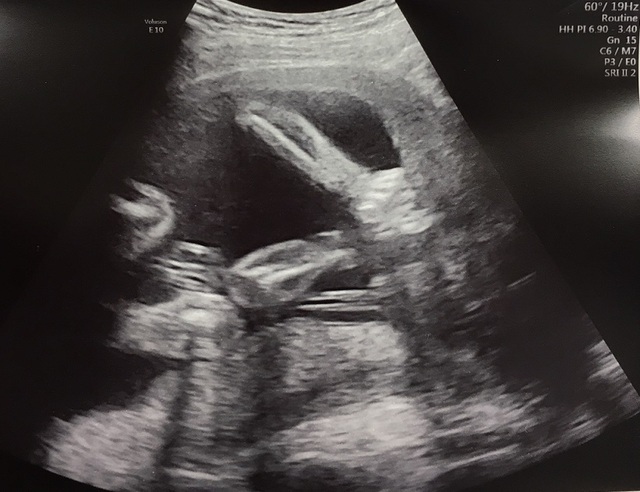

21週6日(21w6d・男の子)|ギンスキー さん(26歳)

エコー写真撮影時のエピソード:

妊娠21週の頃は、胎動もより強く感じるようになってきて、お腹も周りの人から見ても分かるくらい大きくなってきました。

夜寝る前や、電車に乗ってる時など、ふとした時によく動いてくれるのが愛しかったなぁ。

そんな時のエコーに映った可愛い小さな足。

ちゃんと足の指も5つ見えて安心するのと同時に、この可愛い足が蹴ってるのが伝わってるのかなぁとベイビーの存在を更に更に強く感じた思い出のエコー写真です。